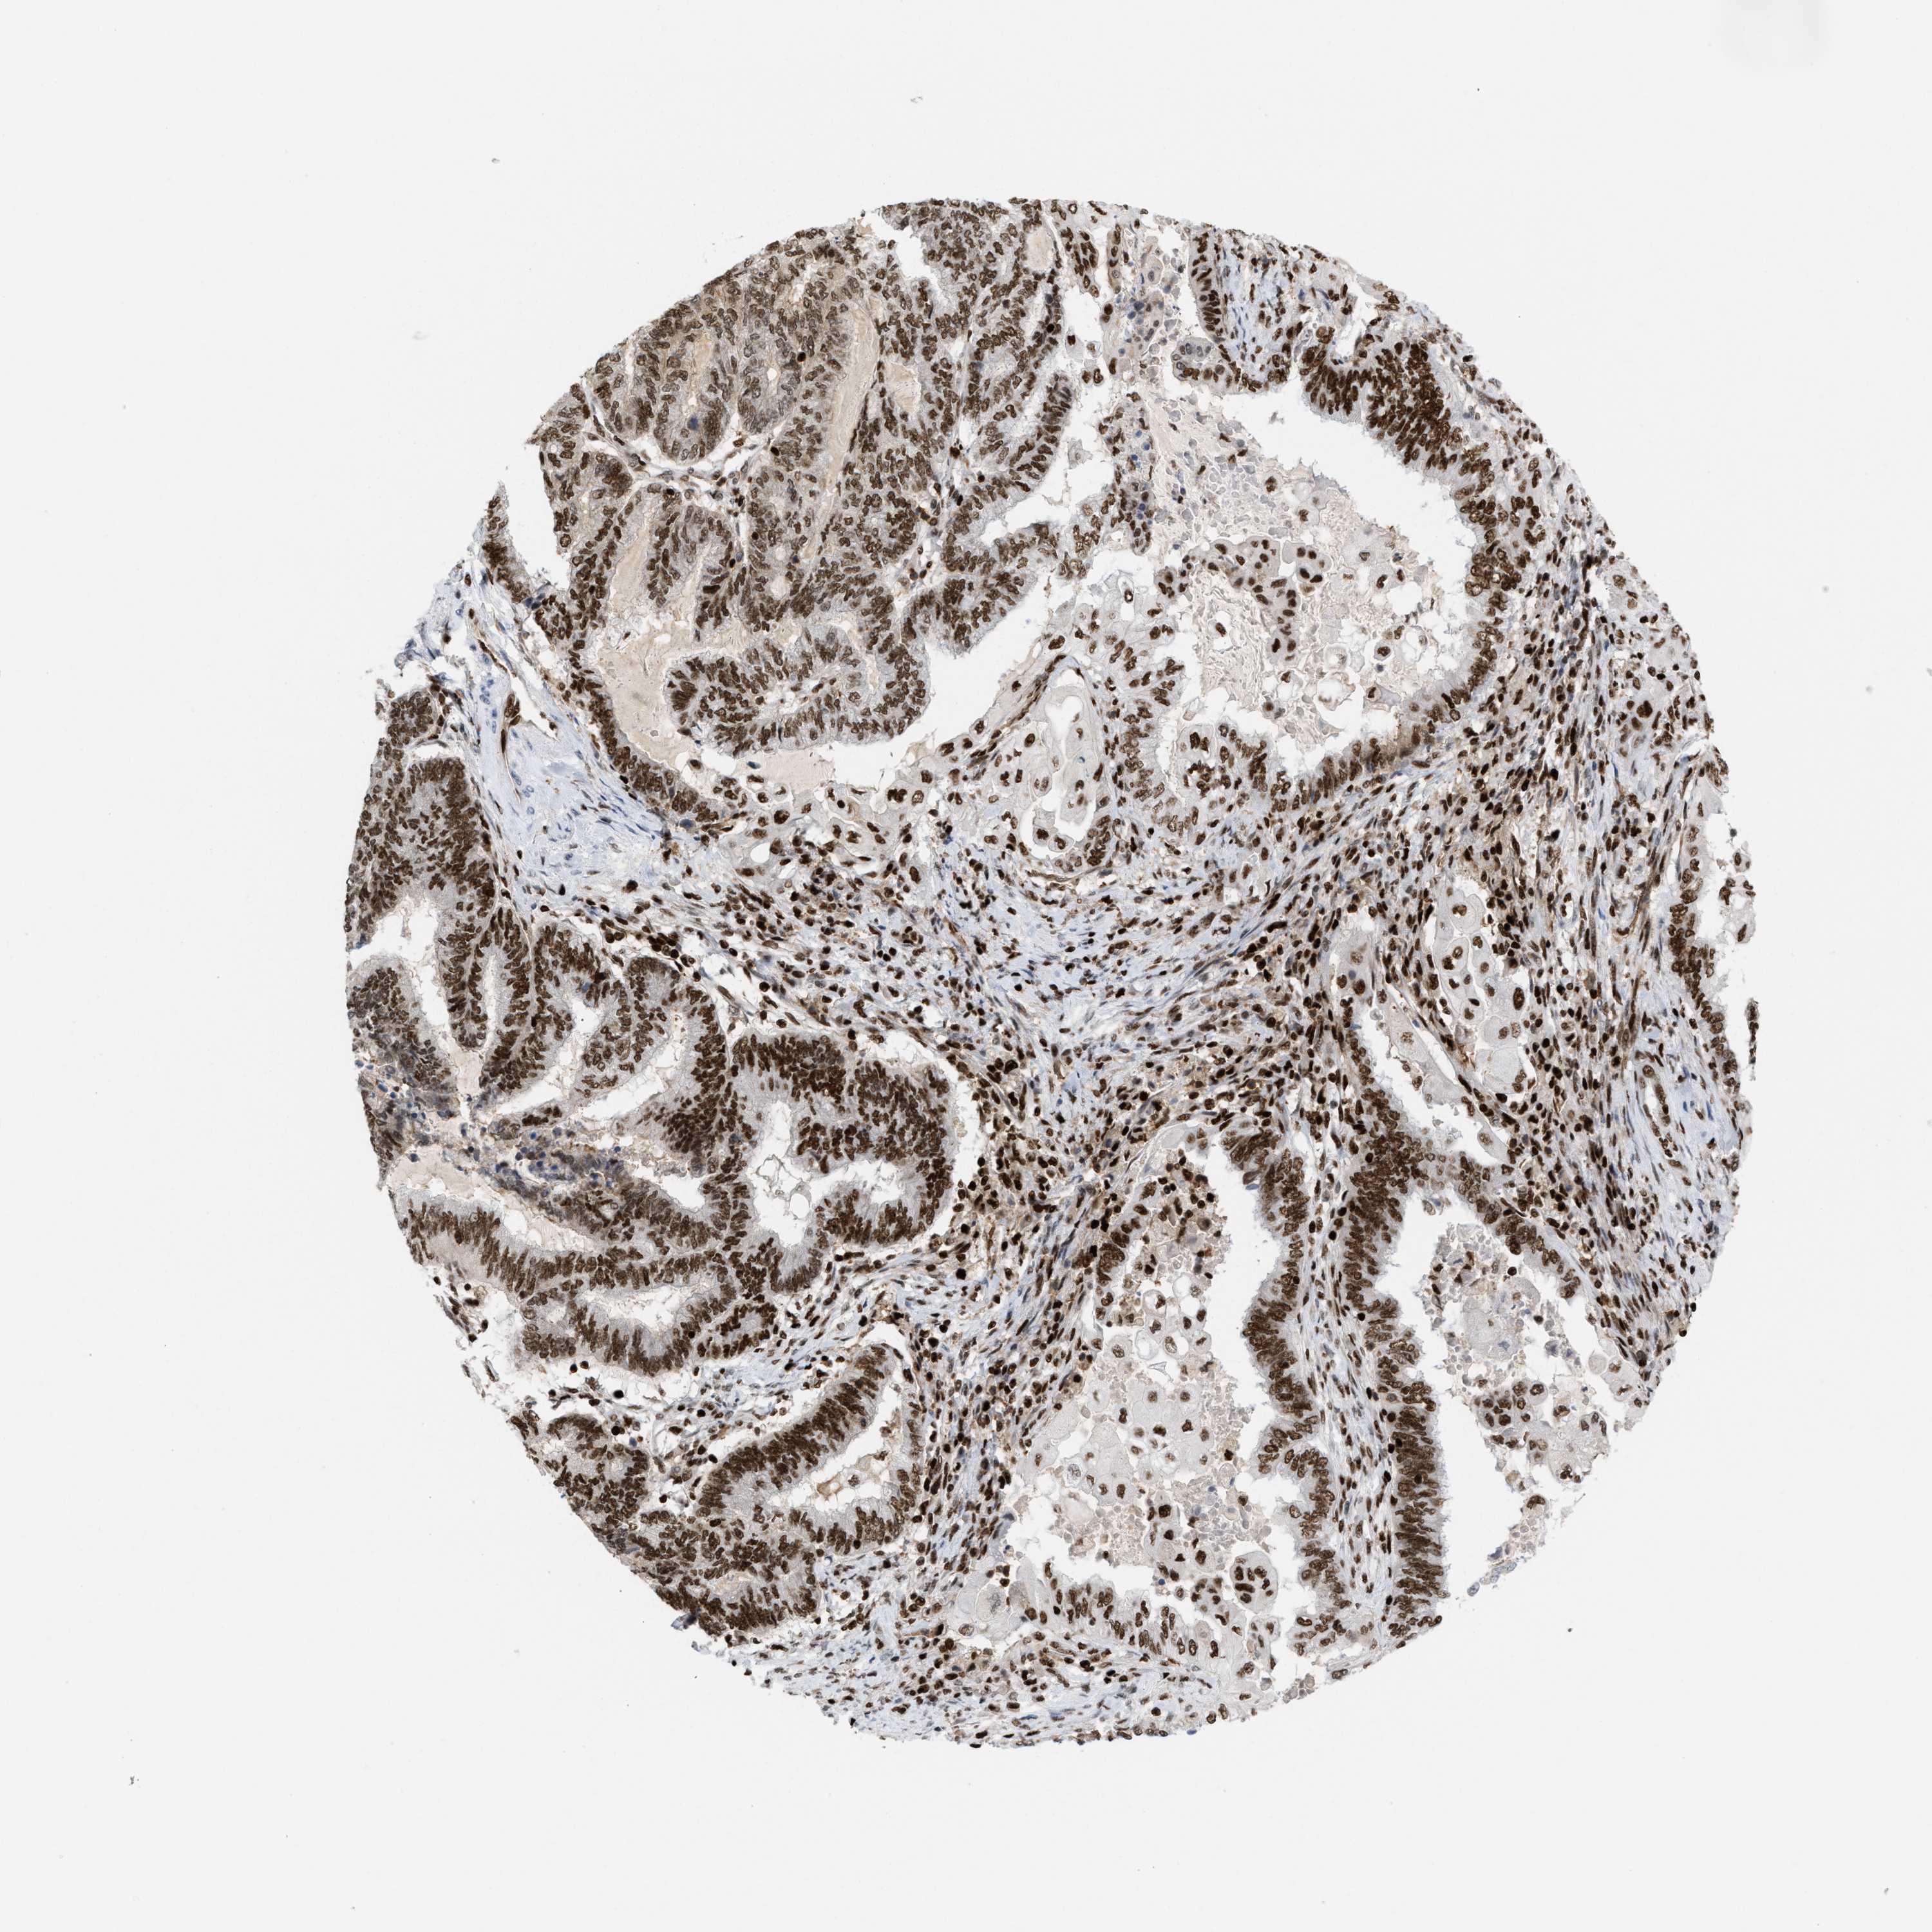

ENDOMETRIAL CANCER - Protein expressioni

A mouse-over function shows sample information and annotation data. Click on an image to view it in a full screen mode. Samples can be filtered based on level of antibody staining by selecting one or several of the following categories: high, medium, low and not detected. The assay and annotation is described here.

Note that samples used for immunohistochemistry by the Human Protein Atlas do not correspond to samples in the TCGA dataset.

Antibody stainingi

Antibody staining in the annotated cell types in the current human tissue is reported as not detected, low, medium, or high, based on conventional immunohistochemistry profiling in selected tissues. This score is based on the combination of the staining intensity and fraction of stained cells.

Each image is clickable and will lead to virtual microscopy that enables deeper exploration of all samples and also displays staining intensity scores, fraction scores and subcellular localization as well as patient and tissue information for each sample.

Antibody HPA022961

Antibody HPA024457

Staining

High

Medium

Low

Not detected

Intensity

Strong

Moderate

Weak

Negative

Quantity

>75%

75%-25%

<25%

None

Location

Nuclear

Cytoplasmic/membranous

Cytoplasmic/membranous,nuclear

Adenocarcinoma, NOS

Adenoma, NOS